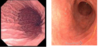

What is the difference between the two endoscopies?

What is the difference between the to images of autoimmune gastritis?

In the severe autoimmune gastritis, there is a bunch of space between glands and there are very few glands

additional goblet cells

you What are the indicated signs of autoimmune gastritis with atrophy?

you usualy don’t have an active phase with PMNs like in helicobacter